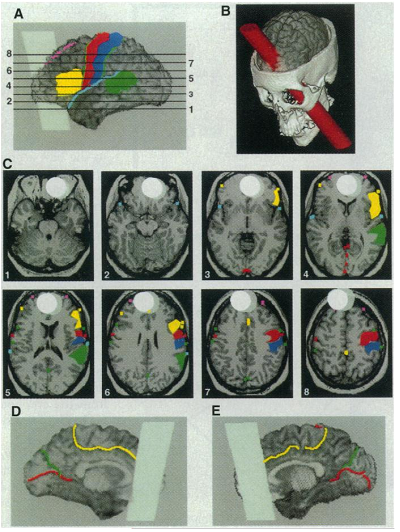

盖奇的故事,引起了科学家对前额叶功能的重视。但直到20世纪末期,神经科学家们才真正开始研究前额叶的功能。南加州大学的安东尼奥·达马西奥(Antonio R. Damasio)与汉娜·达马西奥(Hanna.Damasio)让人们重新关注盖奇的个案。1994年,他们通过计算机和盖奇的头骨,模拟出了盖奇受伤的大脑部位(见下图),这一结果发表在《科学》杂志上(Damasio, Grabowski, Frank, Galaburda, & Damasio,1994)。

除了关注于盖奇这个历史人物之外,他们的研究团队还关注现代的“盖奇”,即与盖奇类似的前额叶受损伤病人。早在1990年,他们就发现,前额叶受损的病人,他们在看到社会性信息时,其生理反应就与普通人不同。1999年,他们报告了两名儿童期就前额叶受损的个案,发现他们与文献中对盖奇的描述相似:决策时只关注短期的利益而不在乎长期的后果、更加倾向于冲动性的攻击(Anderson, Bechara, Damasio, Tranel, Damasio,1999),这些行为的模式与具有反社会人格的个体非常相似。在一系列的研究中,达马西奥发现前额叶受损的病人决策能力与正常人明显不同,冲动是最明显的特征之一。

如果说前额叶损伤的病例提供了少量关于前额叶在冲动控制功能上的因果证据,那么对那些具有反社会人格的个体所进行的研究,则提供了更加丰富的证据。宾州大学犯罪学系的阿德里安·雷恩(Adrian Raine)教授于1997年发表的研究发现,杀人犯的前额叶与正常人不一样,他们前额叶的葡萄糖代谢水平更低。此后,雷恩的研究团队对暴力犯和精神病态进行了一系列的神经成像方面研究。2009年,他们分析了40多项关于反社会个体的神经成像研究的结果,发现多个研究结果比较一致,均揭示了具有反社会行为的个体在前额叶结构与功能上的缺陷(Yang & Raine, 2009)。在新书《The Anatomy of Violence》中,雷恩教授系统地阐述了前额叶结构与功能的缺陷与反社会行为关系的研究成果。